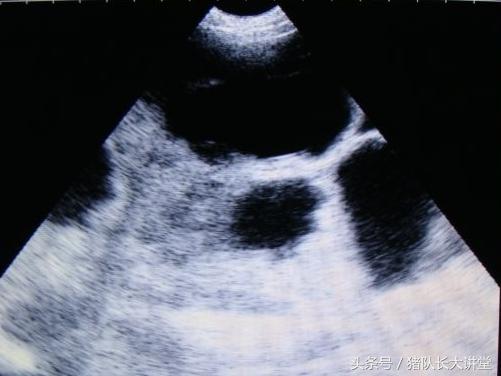

23天的B超图

27天图

中间的黑球是初期胚胎